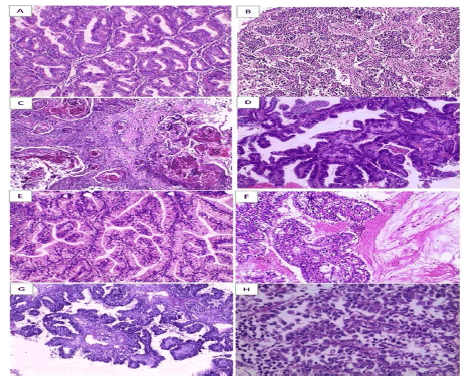

Paraffin blocks from 70 of endometrial carcinoma cases, 52 cases of endometrioid type and 18 cases of nonendometrioid type. The clinicopathological features of the studied cases of endometrial carcinoma are summarized in (Table 1). Age ranged from 35 – 84 years with a mean of 58.5 ± 14.35 years. According to binary grade classification system, studied cases were graded into: Low grade: There were 43 cases including 28 cases were endometrioid adenocarcinoma of usual type, 2 cases was endometrioid adenocarcinoma with squamous differentiation, 7 cases were endometrioid adenocarcinoma with villoglandular pattern, 2 cases were endometrioid adenocarcinoma with secretory pattern, and 4 cases were endometrioid adenocarcinoma with mucinous differentiation. High grade: There were 27 cases including 6 cases were endometrioid adenocarcinoma of usual type, 3 cases were endometrioid adenocarcinoma with squamous differentiation, 11 cases were uterine papillary serous carcinoma, and 7 cases were clear cell endometrial carcinoma. Tumour staging was determined according to FIGO stage of tumours of the Uterine Corp (American Joint Committee on Cancer) 70 cases were categorized into: stage IA was 24 cases representing (34.3%), stage IB was 34 cases representing (48.6%), stage II was 8 cases representing (11.4%), stage IIIA was 3 cases representing (4.3%) and stage IVA was 1 case representing (1.4%). Myometrial invasion ≥ 50% occurred in 46 (65.71%) cases and below 50% in 24 (34.29%) cases. Lymphovascular invasion was detected in 39 (55.7%) cases (Figure 1)

Figure 1: Histopathological variants of studied cases of endometrial carcinoma (H&E × 200) (A) Low grade endometrioid adenocarcinoma of usual type (B) High grade endometrioid adenocarcinoma of usual type (C) Endometrioid adenocarcinoma with squamous differentiation. (D) Low grade endometrioid adenocarcinoma with villoglandular pattern (E) Endometrioid adenocarcinoma with secretory pattern (F) Endometrioid adenocarcinoma with mucinous differentiation (G) papillary serous carcinoma (H) Clear cell carcinoma